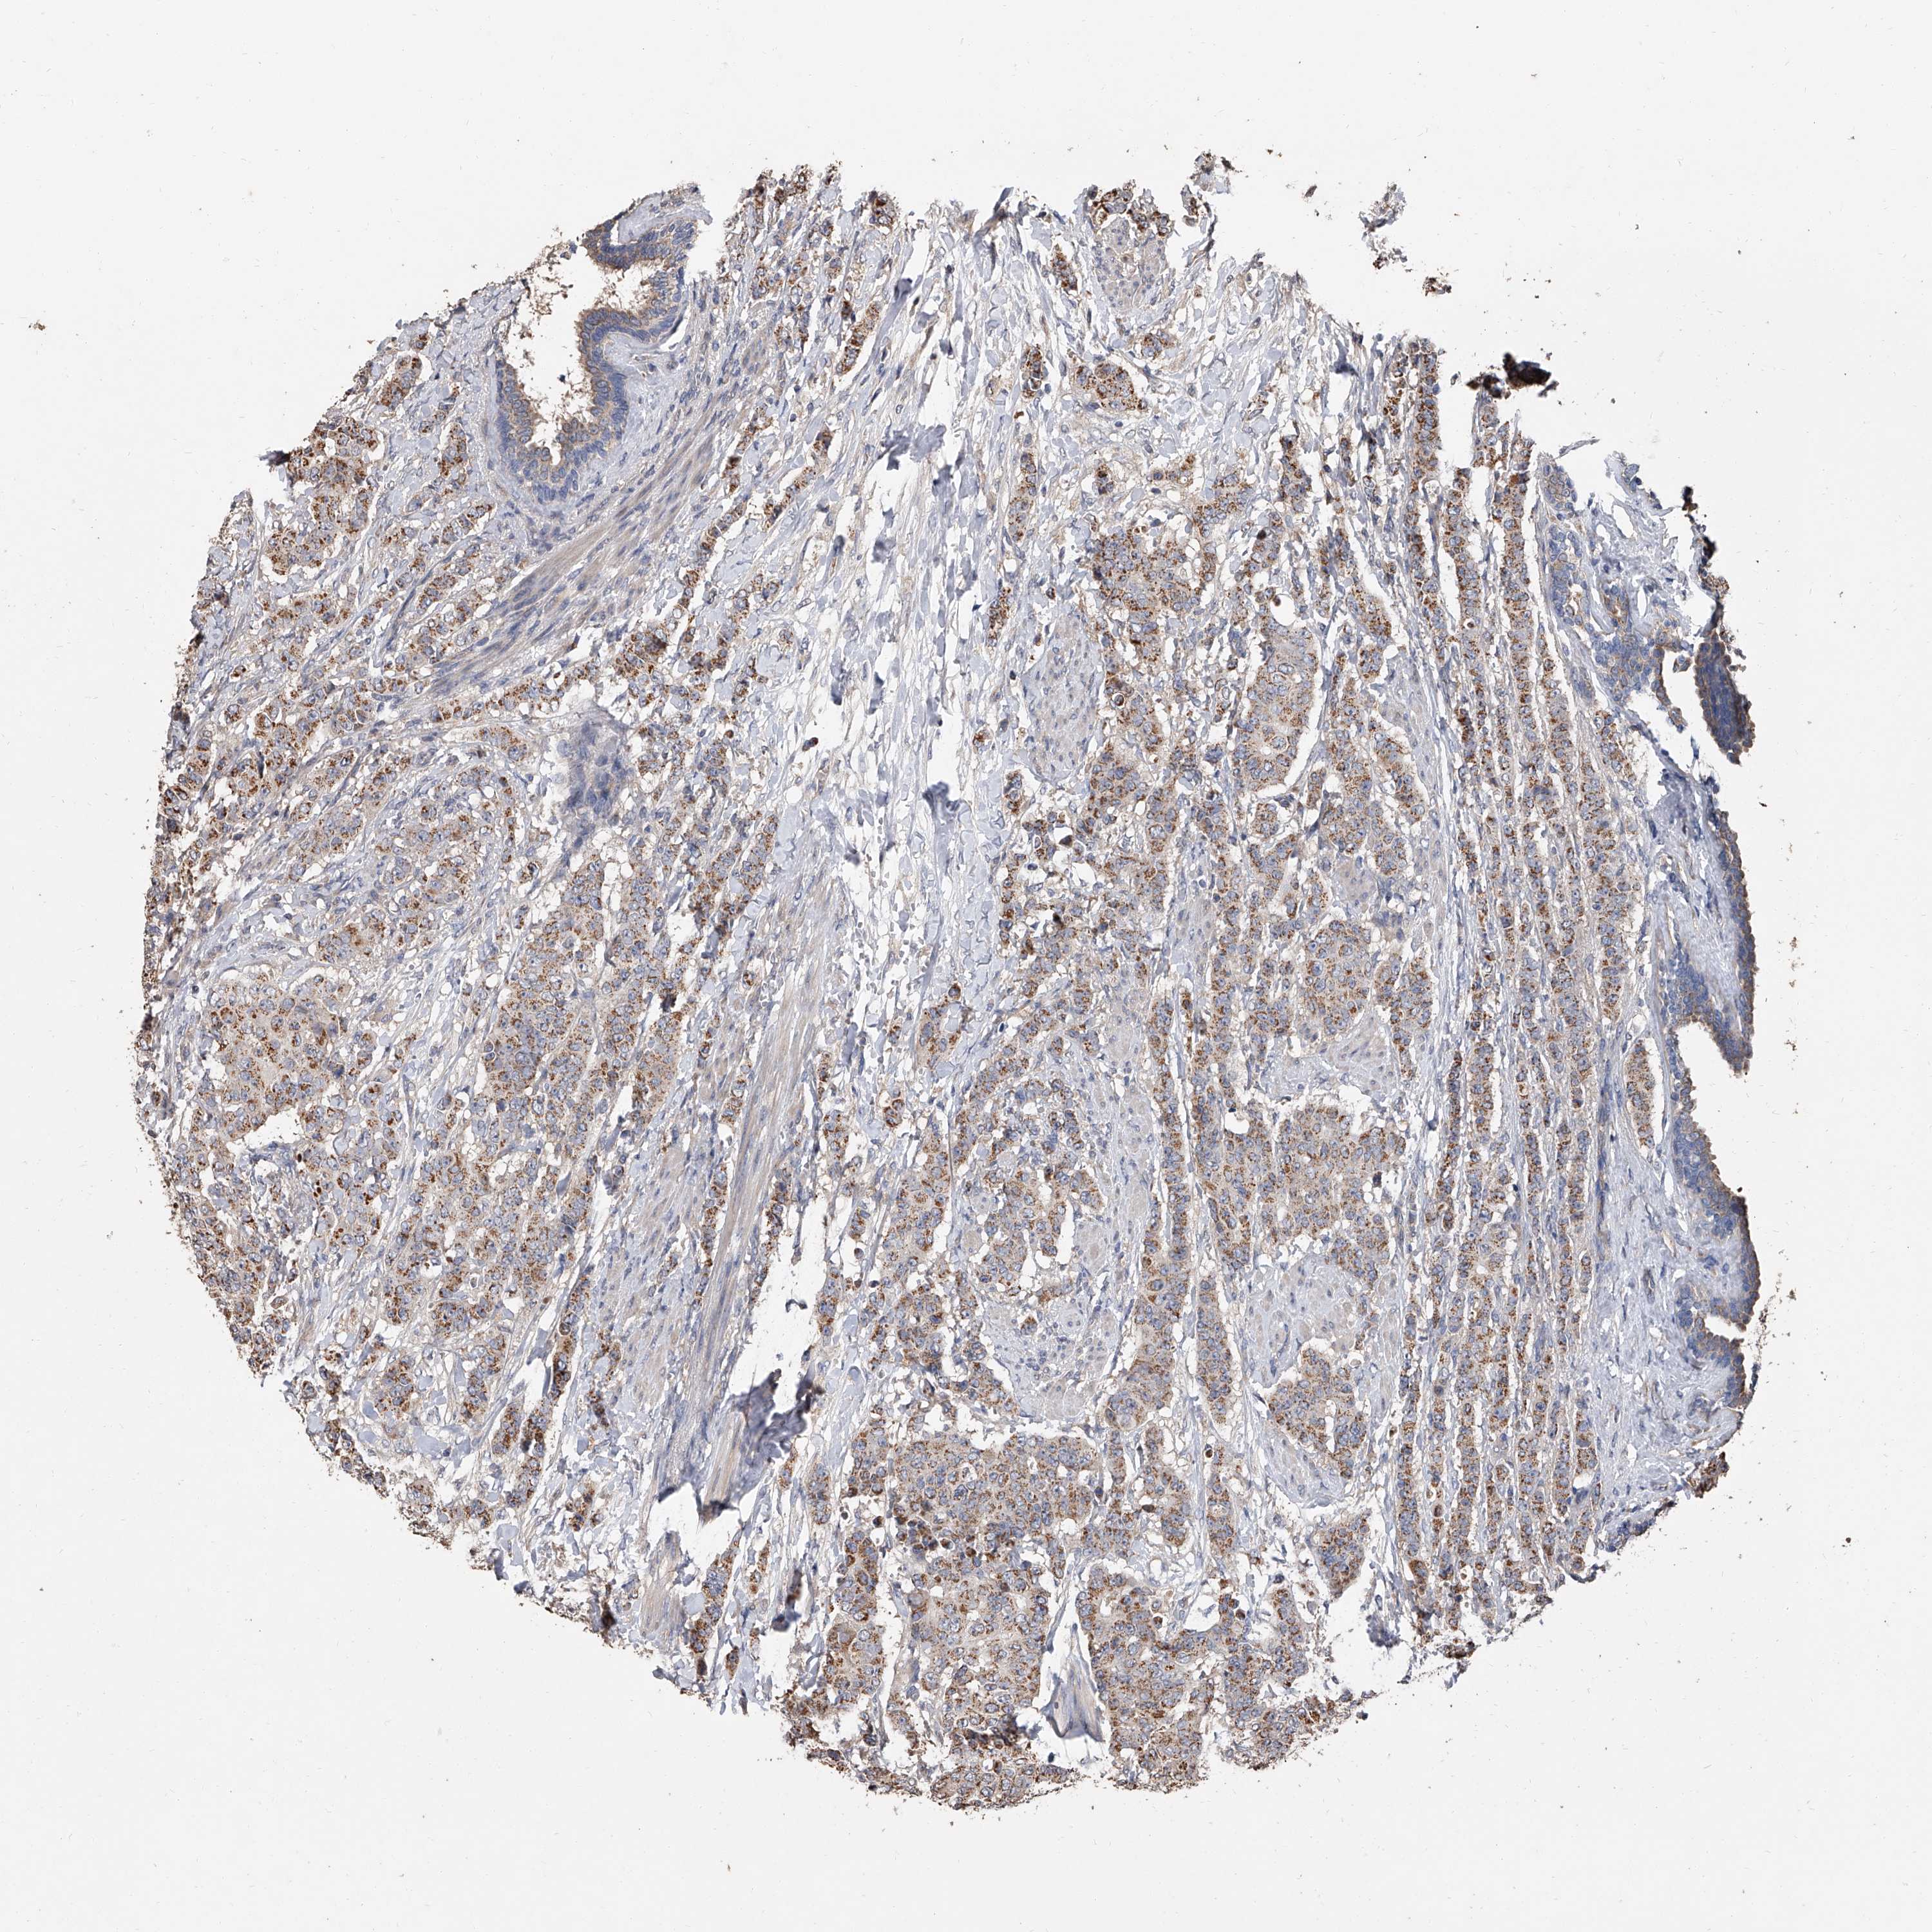

BRCA TCGA BRCA VALIDATION PROTEIN EXPRESSION